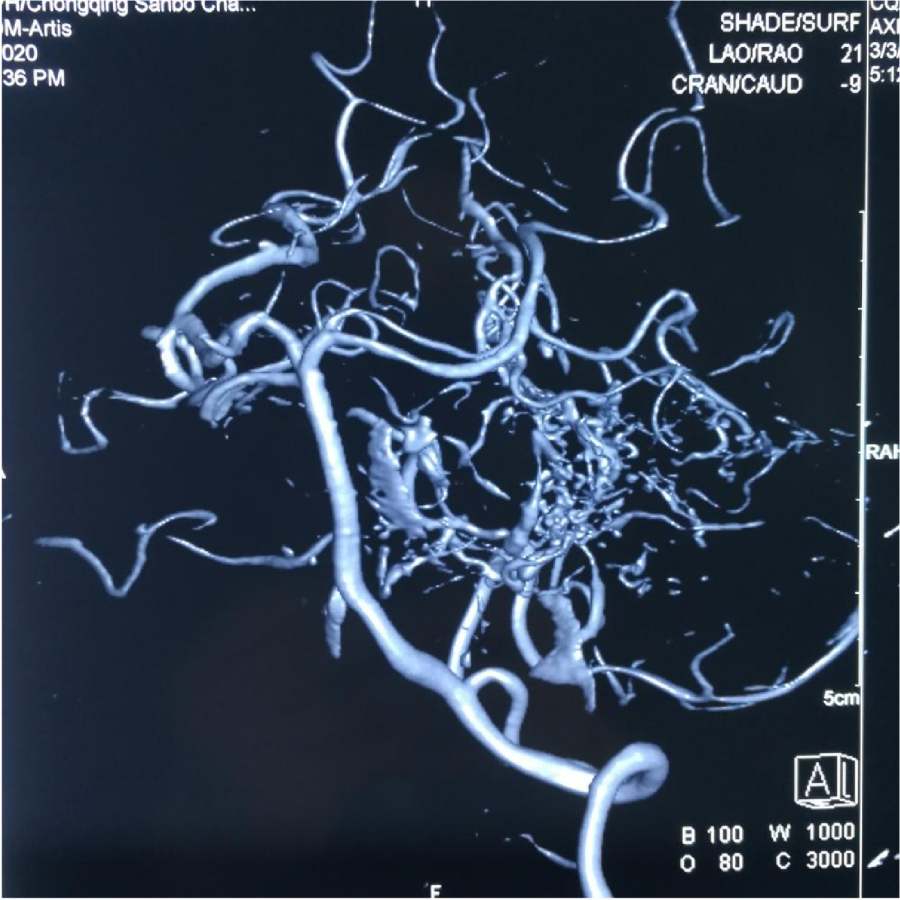

CTA 结果

本次⼊院⾏DSA检查:PICA供⾎区有畸形⾎管团,引流到横窦